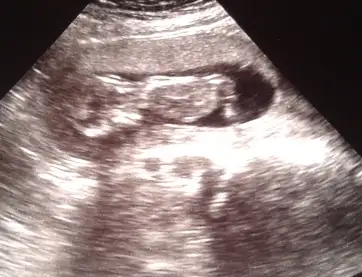

kızlar merhaba, bugün bizim de fotoğrafımız çekildi =)) Sizce kız mı erkek mi??Eki Görüntüle 1036277

cinsiyeti hakkında yorum yapabilir misinizEki Görüntüle 1037575